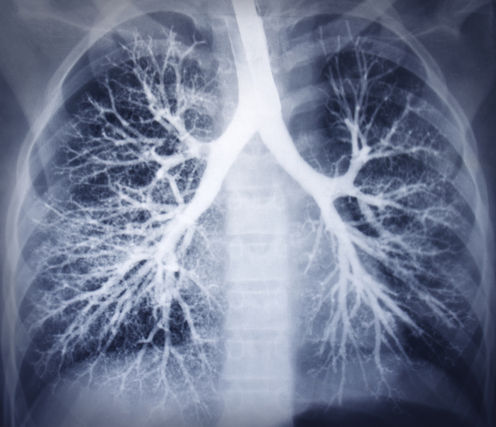

Leaky blood vessels in the lung can lead to acute respiratory distress. Shutterstock

Severe pneumonia can lead to acute respiratory distress syndrome (ARDS), a complication in which the massive leakiness of blood vessels in the lung leads to the fluid build-up, which covers the cells that exchange oxygen and carbon dioxide. Patients usually require mechanical ventilators to force oxygen into the lungs in order to survive.

Pneumonia is one of the most common causes of ARDS but any generalized infection and inflammation that is severe enough to cause massive leakiness of lung blood vessels can cause the syndrome.